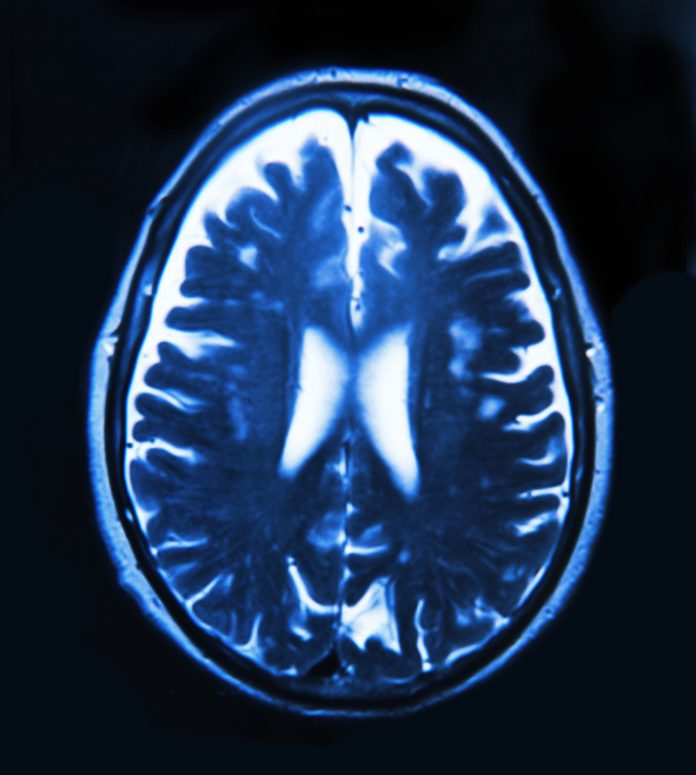

The brain is the key to humanity, providing the immense capabilities of our species. However despite its considerable capacity for self-repair the brain also frequently fails. The costs of poor brain health to Europe are enormous. Traumatic brain injuries, mental illness and cognitive disorders are likely to afflict more than a third of European Union citizens – 179 million people. They cost Europe €798bn per annum – more than any other medical area. This is 7 times the €110bn cost of the 2010 Greek financial rescue, and it is every year.